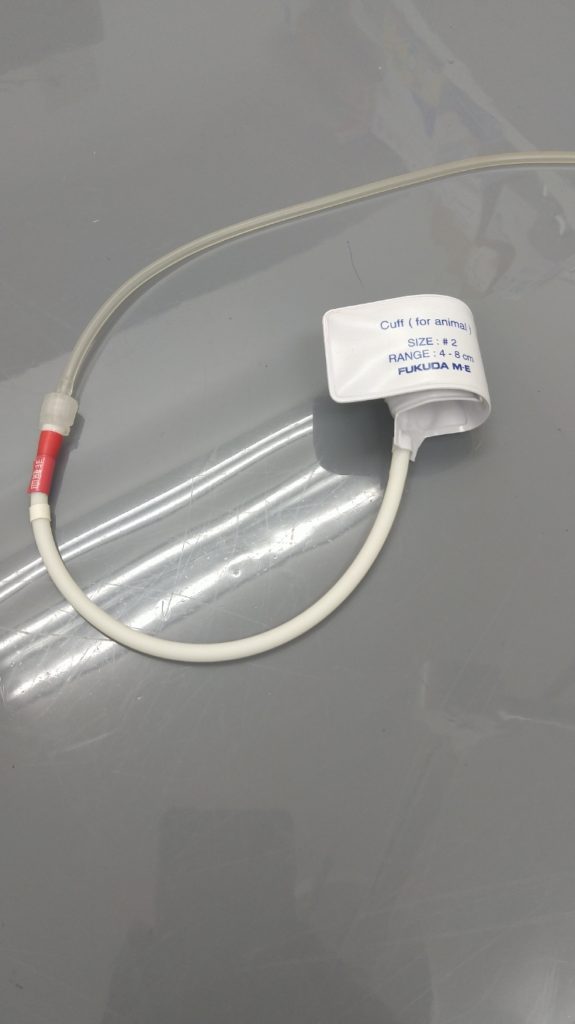

さて、膝蓋骨の脱臼とはどのようなものか?画像を見て説明します。

写真は下半身を正面から撮影したレントゲン写真です。白い矢印(⇨)で指した楕円形の骨が『膝蓋骨』です。本来の位置からは外れてしまっています。またカカトからヒザまでのスネの骨が真っ直ぐ伸びておらず内側へ曲がってしまっています。正しく言うと内転といって骨が内回りに捻じれてしまっています。このような骨格の犬は脱臼しやすいといえるでしょう。

上の画像は脱臼の手術2ヶ月後の写真です。矢印(⇨)が膝のお皿(膝蓋骨)です。正しい位置に戻っています。

膝蓋骨脱臼は診察時に身体検査で見つかる事が多いですが、レントゲン撮影をすることで、より詳しく把握する事ができます。膝蓋骨脱臼について気になる事があれば気軽にご相談ください。